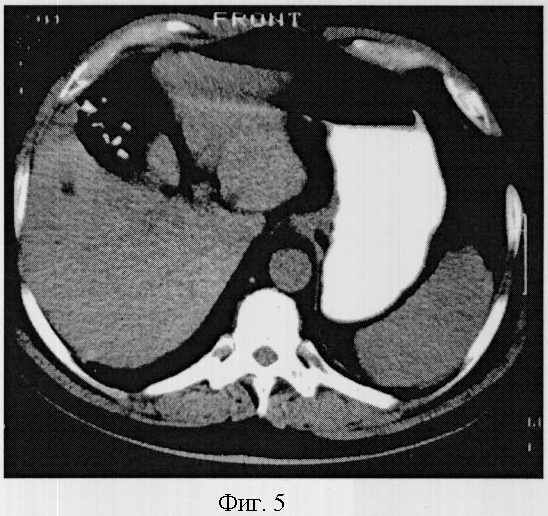

Пример 5. Гипоплазия 3 степени.

Больная Нестеров К.И. 65 лет, проходила обследование по поводу рака желудка. При исследовании отмечается незначительное уменьшение объема печени до 1029,2 см3. Объем левой доли значительно уменьшен и составил 220,6 см. Печень расположена нормопетально, поверхность ее деформирована за счет отсутствия большей части паренхимы четвертого сегмента. Сегментарная ветвь воротной вены при нативном исследовании не визуализируется. Структура паренхимы однородная, плотность 63 HU. Объем четвертого сегмента печени составил 26,2 см3, а коэффициент К=0,14, что соответствовало гипоплазии 3 степени (фиг.5).